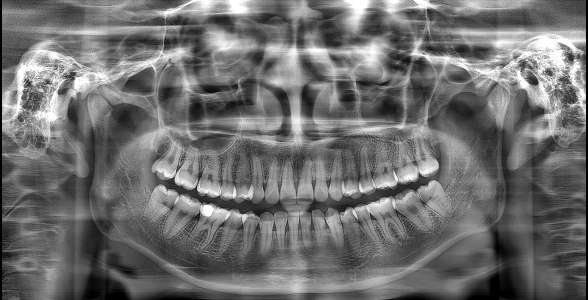

▲“ "The Effect of 'PD' Technology in Panoramic Images"

▲From left to right: Original Image, Mainstream Algorithm, "PD" Technology

▲Advantages of "PD" Technology: Deep Restoration of Image Details